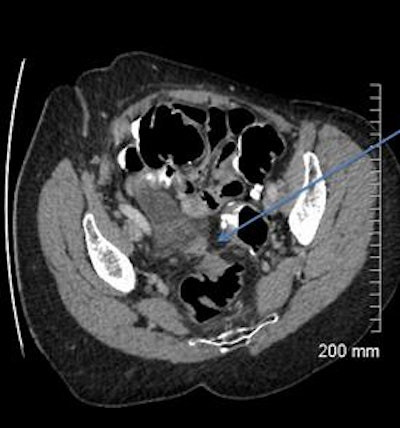

A 68-year-old woman with a fistula, categorized as C1D4E2, between the diverticular sigmoid and the vaginal vault. All images courtesy of Dr. John Hanson.

A 52-year-old man with a benign stricture, categorized as C4E1D4. The arrows highlight the smooth gradual transmural thickening within a diverticular laden sigmoid colon. Benign stricture was confirmed with surgical resection.